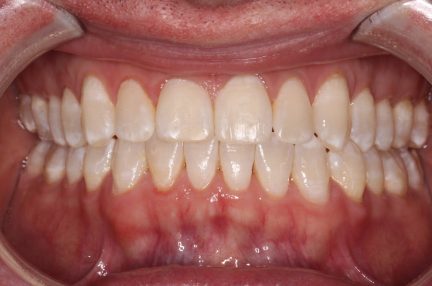

Résultats obtenus

- Relation de classe III maintenue

- Surplomb et recouvrement normaux atteints

- Lignes médianes coïncidentes

- Tous les objectifs du traitement ont été atteints cas

- Des arcades harmoniques ont été réalisées

- La béance antérieure de classe III a été corrigée par une combinaison d'égression active absolue des dents antérieures supérieures ainsi que d'une inclinaison des incisives

- La rétraction des dents antérieures inférieures en utilisant l'espace existant ainsi que l'espace gagné en effectuant une réduction interproximale et avec l'usure élastique de classe III ont contribué à la correction de la béance antérieure